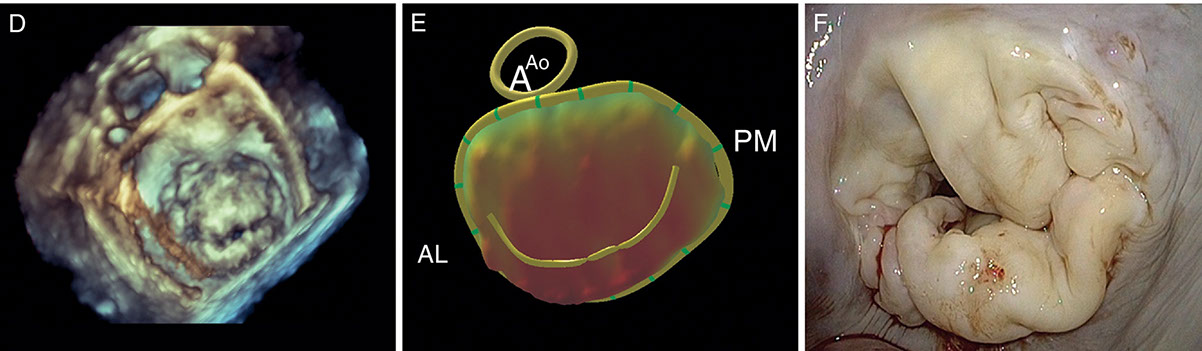

- Ecocardiograma Doppler 3D para paciente adulto y pediátrico. Es un examen que emplea ondas sonoras para crear una imagen en movimiento del corazón.

- Ecocardiograma Transesofágico. Es un examen en el que se hace pasar un pequeño transductor a través del esófago para obtener una imagen más clara de la estructura del corazón.